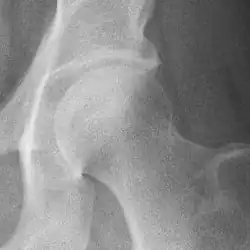

Osteoarthritis of the hip joint may also be graded by Tönnis classification. There is no consensus whether it is more or less reliable than the Kellgren-Lawrence system.[8]

Severe (Tönnis grade 3) osteoarthritis of the hip.

Tönnis classification[9]

Grade Description

0 No osteoarthritis signs

1 Mild:

• increased osteosclerosis

• minor joint space narrowing (normal joint space is at least 2 mm at the superior acetabulum)[7]

• no or minor loss of head sphericity

2 Moderate:

• small bone cyst

• moderate joint space narrowing

• moderate loss of head sphericity

3 Severe:

• large bone cysts

• severe joint space narrowing, or joint space obliteration

• severe deformity of the head